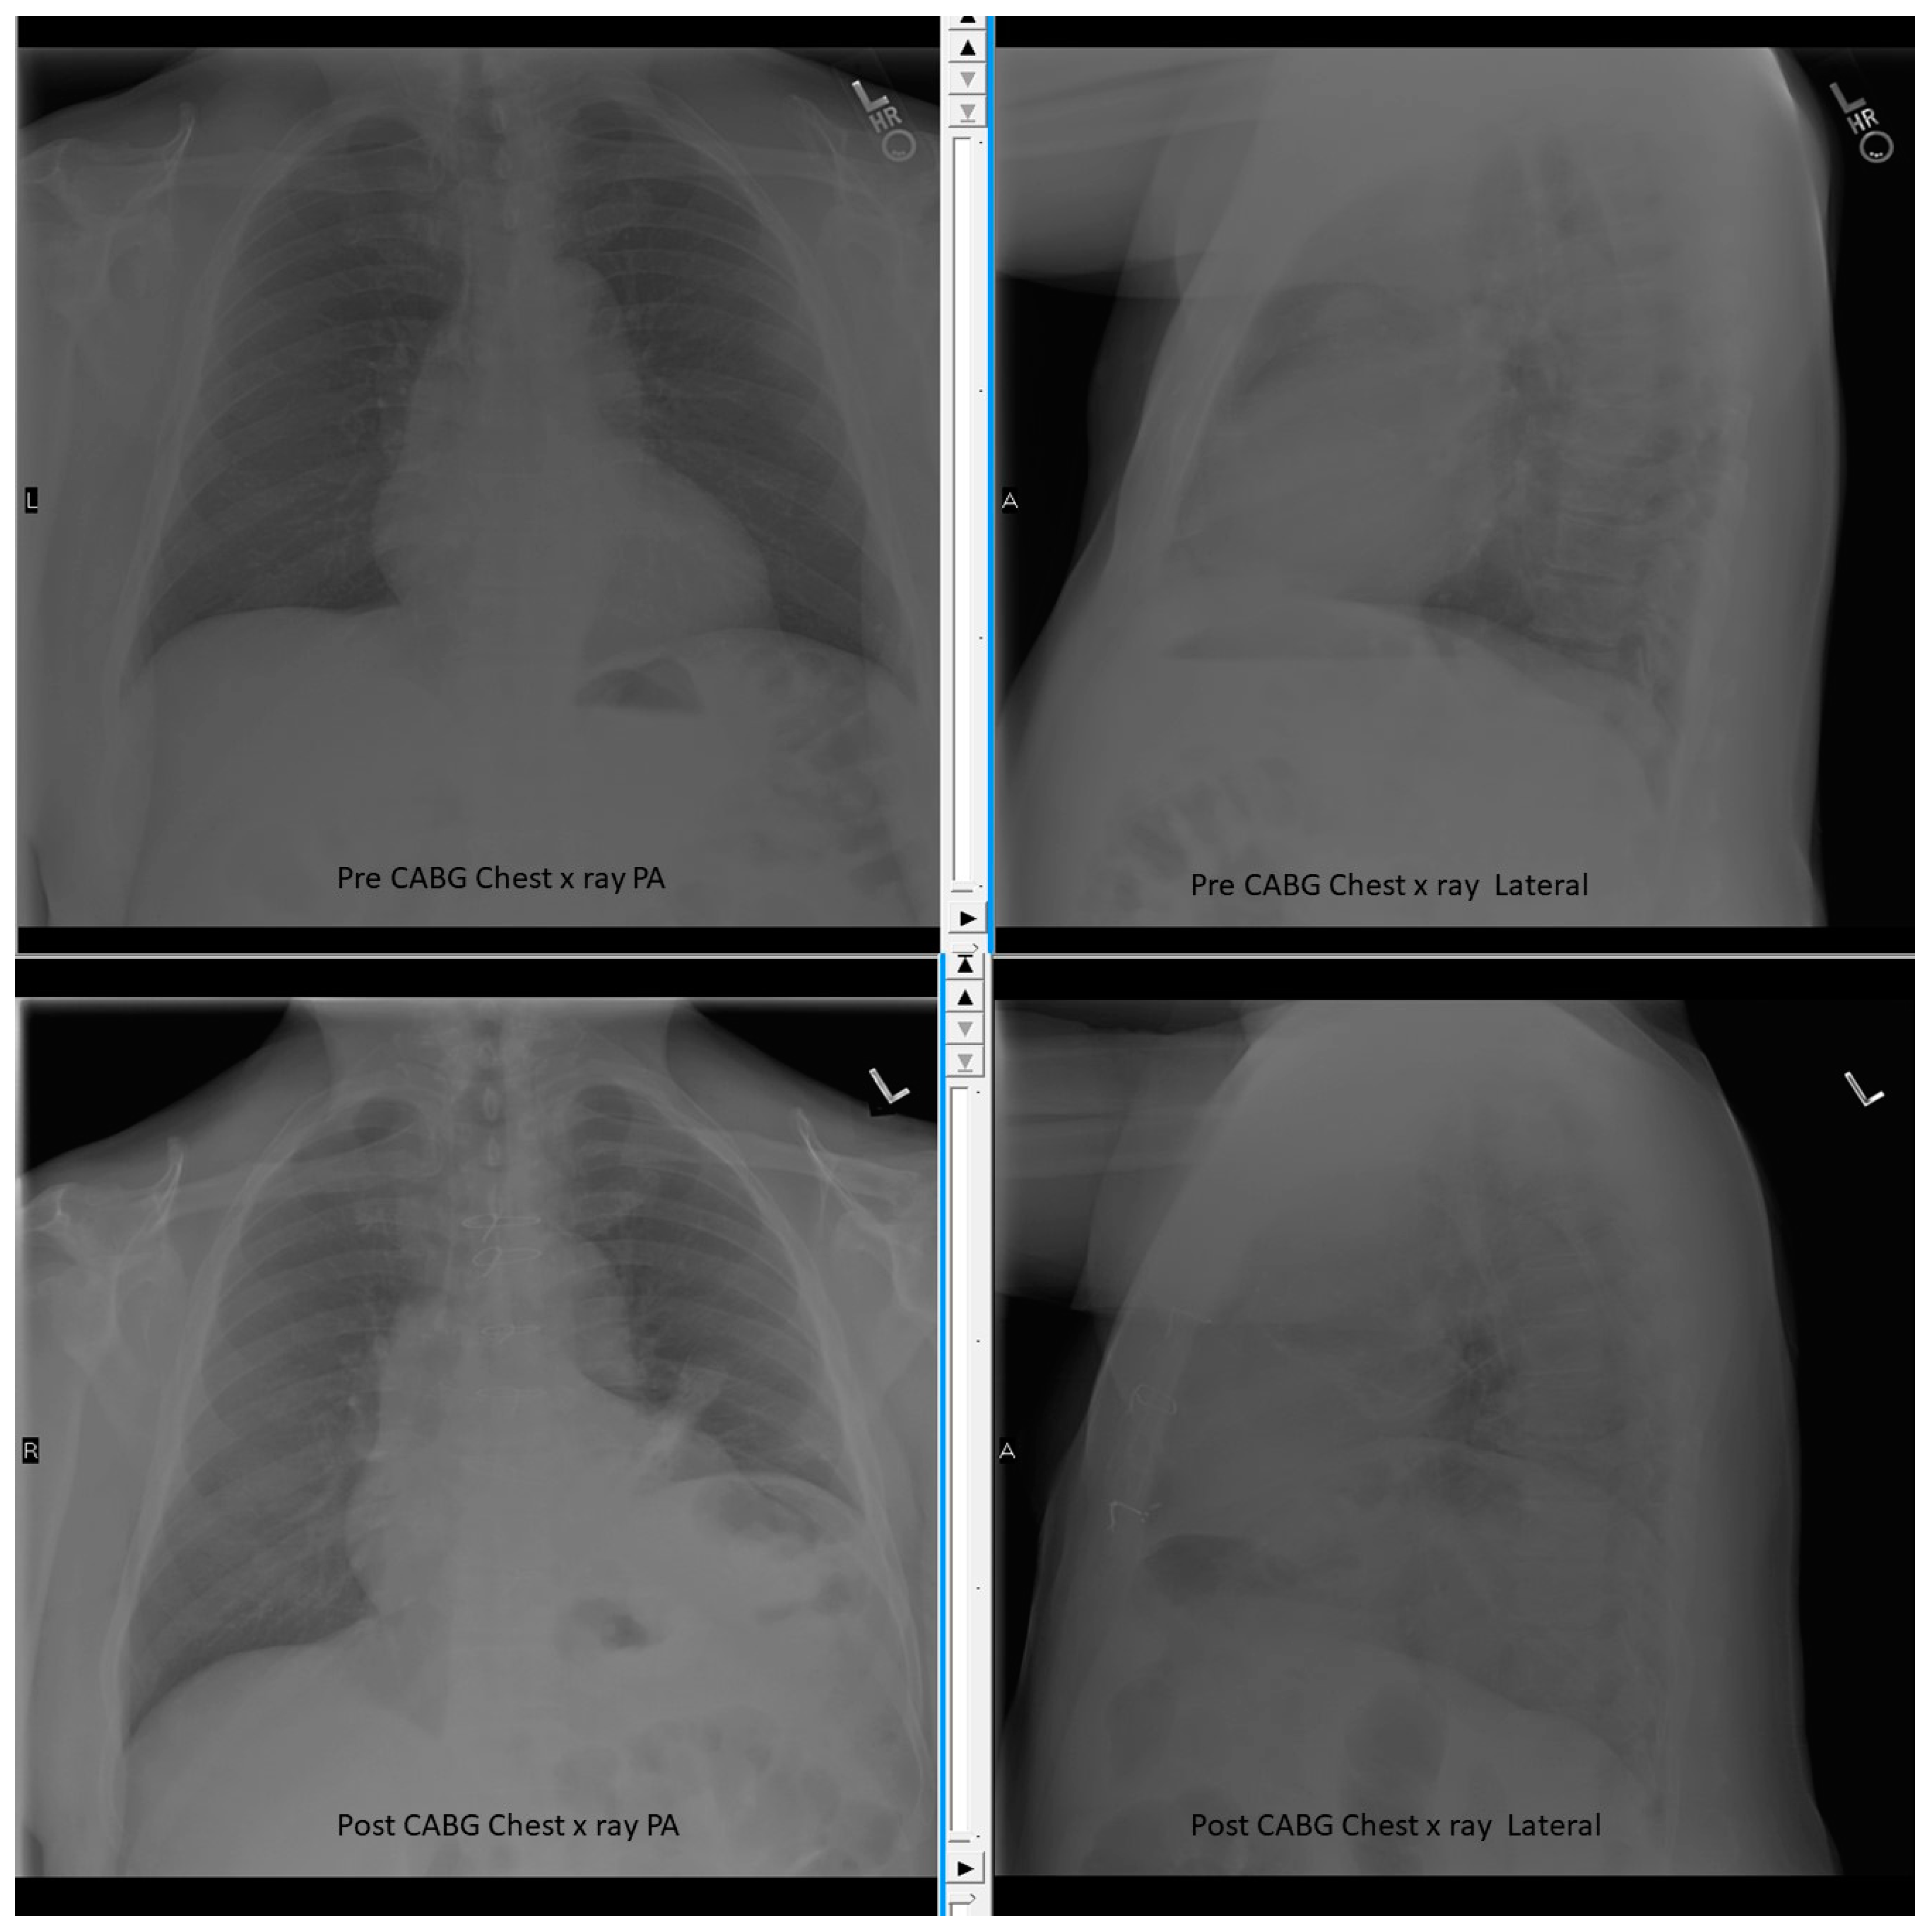

- Aguirre, V.J.; Sinha, P.; Zimmet, A.; Lee, G.A.; Kwa, L.; Rosenfeldt, F. Phrenic nerve injury during cardiac surgery: Mechanisms, management and prevention. Heart Lung Circ. 2013, 22, 895–902. [Google Scholar] [CrossRef] [PubMed]

- Dimopoulou, I.; Daganou, M.; Dafni, U.; Karakatsani, A.; Khoury, M.; Geroulanos, S.; Jordanoglou, J. Phrenic nerve dysfunction after cardiac operations: Electrophysiologic evaluation of risk factors. Chest 1998, 113, 8–14. [Google Scholar] [CrossRef] [PubMed]

- Wheeler, W.E.; Rubis, L.J.; Jones, C.W.; Harrah, J.D. Etiology and prevention of topical cardiac hypothermia-induced phrenic nerve injury and left lower lobe atelectasis during cardiac surgery. Chest 1985, 88, 680–683. [Google Scholar] [CrossRef] [PubMed]

- Curtis, J.J.; Nawarawong, W.; Walls, J.T.; Schmaltz, R.A.; Boley, T.; Madsen, R.; Anderson, S.K. Elevated hemidiaphragm after cardiac operations: Incidence, prognosis, and relationship to the use of topical ice slush. Ann. Thorac. Surg. 1989, 48, 764–768. [Google Scholar] [CrossRef]

- Efthimiou, J.; Butler, J.; Woodham, C.; Benson, M.K.; Westaby, S. Diaphragm paralysis following cardiac surgery: Role of phrenic nerve cold injury. Ann. Thorac. Surg. 1991, 52, 1005–1008. [Google Scholar] [CrossRef]

- Chetta, A.; Rehman, A.K.; Moxham, J.; Carr, D.H.; Polkey, M.I. Chest radiography cannot predict diaphragm function. Respir. Med. 2005, 99, 39–44. [Google Scholar] [CrossRef] [PubMed]

- Nason, L.K.; Walker, C.M.; McNeeley, M.F.; Burivong, W.; Fligner, C.L.; Godwin, J.D. Imaging of the diaphragm: Anatomy and function. Radiographics 2012, 32, E51–E70. [Google Scholar] [CrossRef] [PubMed]